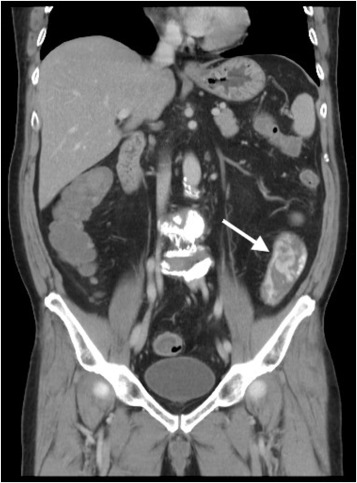

The two endoclips remained in situ , and active bleeding was observed in the narrow gap between the two endoclips. This finding explained the ineffective clipping and the difficult endoscopic approach to the bleeder source. An attempt with a heat probe, coagulation forceps, and further clipping all failed to approach the bleeder. We further attempted to administer an injection of diluted epinephrine in the base of the stalk remnant, and the remnant slowly began rising, giving the appearance of a new polyp. An endoloop was successfully placed beneath the two previously placed endoclips using the tulip-bundle technique, and the bleeding was successfully controlled ( Figure 3 ). The patient was discharged 3 days later without further bleeding.

Endoscopic view after injection and application of an endoloop using the ...

Figure 3.

Endoscopic view after injection and application of an endoloop using the tulip-bundle technique for successful hemostasis.